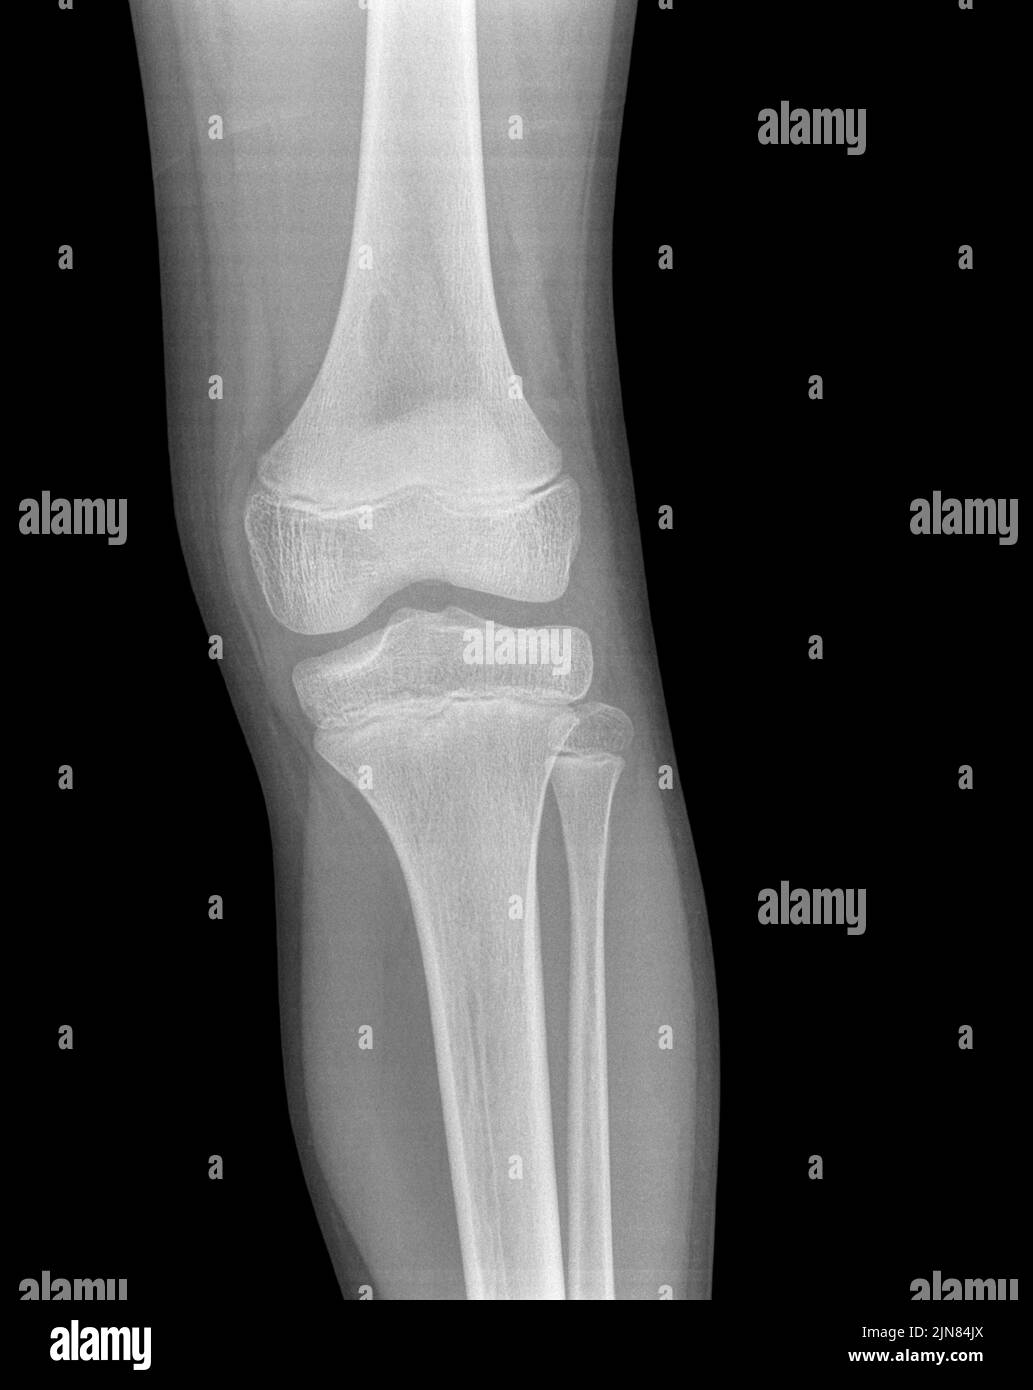

Lead Poisoning Knee X Ray . Learn about the causes, symptoms, diagnosis, and treatment of lead poisoning, a condition caused by occupational and environmental exposure to lead. Manifestations differ based on a myriad of. Learn about the causes, symptoms, and diagnosis of lead poisoning, a chronic environmental illness affecting children and adults. This article covers acute and. See images of lead lines, foreign bodies,. Lead toxicity is a multisystem disease produced by inhalation or ingestion of lead. Learn about blood lead screening and confirmatory testing guidelines for children and adults at risk of lead exposure. Find out how to interpret blood lead levels and other clinical modalities.